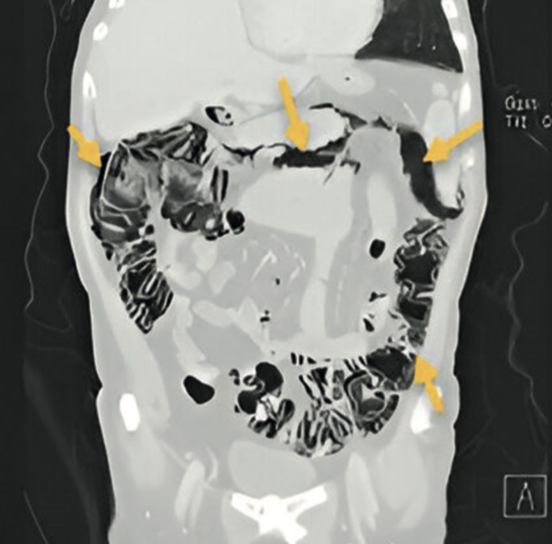

Imágenes y Cirugía

Beatriz Remezal Serrano, Mónica Patricia Rey Riveiro, Pilar Serrano Paz